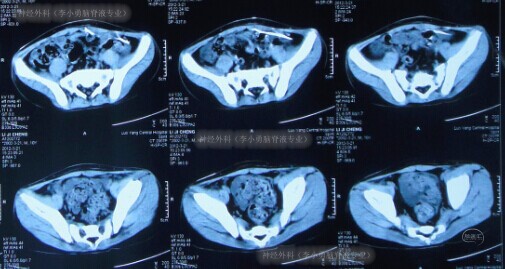

医生经患儿分流管泵抽吸脑脊液进行细菌培养,并给予患儿抗炎、脱水等处理。3天后细菌培养结果回报为阴性,继续抗炎治疗10天后即2012年3月13日,但症状仍无好转;当天查腹部CT显示分流管腹腔端周围包裹性积液(图-2)。

图-2:2012年3月13日腹部CT

腹腔镜下分流管腹腔端修正术后第7天即2012年3月21日,症状消失出院,出院时查腹部CT显示左侧腹腔内可见分流管腹腔端,其周围无异常(图-4)。

图-4:2012年3月21日腹部CT